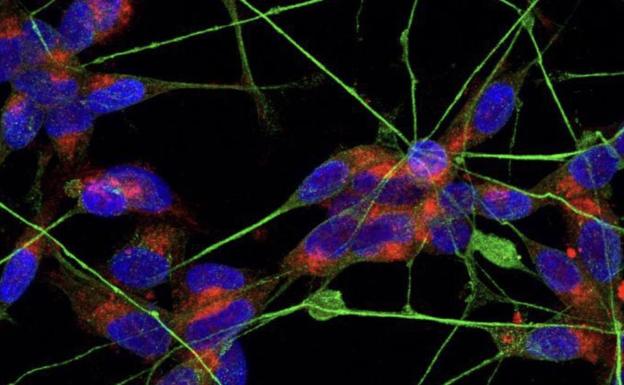

En un intento por descifrar las bases celulares de los efectos de la marihuana, un estudio ha observado que esta planta provoca efectos terapéuticos o adversos según la región celular que activen